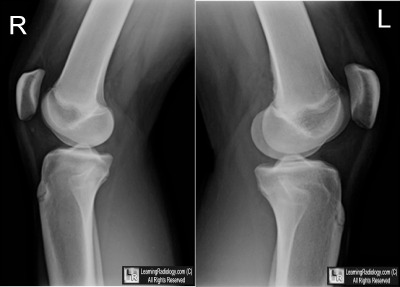

Case of the Week 568

What is the most likely diagnosis?

• 11 year-old male who struck left knee

Lateral Radiographs of both Right and Left Knees

3. Cortical Desmoid

Cortical Desmoid

• AKA Distal Femoral Metaphyseal Irregularity, Avulsive Cortical Irregularity, Periosteal Desmoid

• Age range: 3-17 years, most common 10-15

• Cortical irregularity at the posterior, medial and distal femur deep to the attachments of medial gastrocnemius or distal adductor magnus